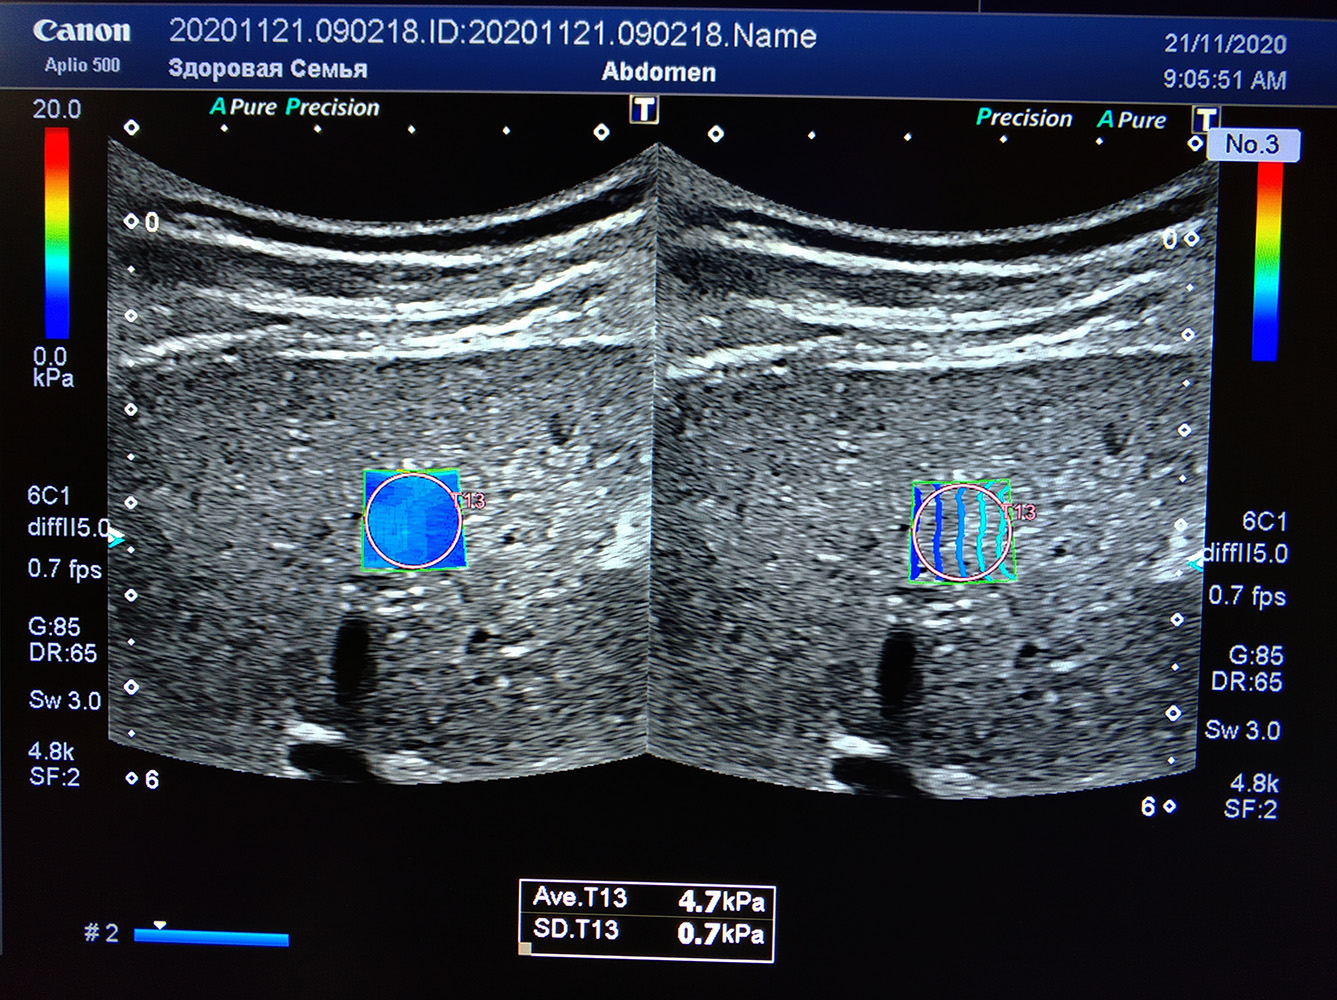

Aplio 500 значительно упрощает работу путем создания специальной карты отображения сдвигов поперечных волн. Выглядит это как окно, заполненное цветными линиями. В случае приближения плотной структуры к полю исследования или прилегания крупного сосуда, результаты будут не достоверными. Такое НЕ оптимальное ЭХО окно будет неизбежно препятствовать исследованию. Именно на эти проблемы и реагируют линии, отображающие сдвиг. Чем линии прямее – тем качественнее будет результат. Таким образом, вы не только сразу видите качество ЭХО окна и места измерений, но и можете выбрать наиболее оптимальные участки в поле.

Однако карта там не одна, в режиме двух экранов мы видим и вторую карту – разметку скорости сдвиговых волн, из которых сразу можно автоматически пересчитать плотность в килопаскалях. Синие цвета – мягкие участки, красная расцветка говорит о выраженной плотности. Измерение проводится по участку с равномерной окраской, это позволяет избегать артефактов и мелких связок. Качество проведенного исследования резко возрастает.